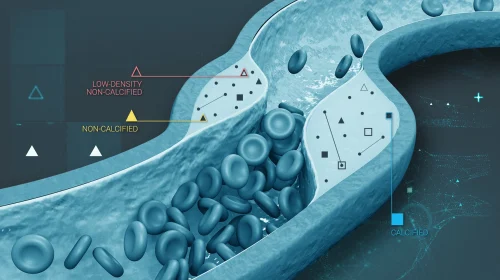

Heart Plaque

Plaque is made up of deposits of fatty substances, cholesterol, cellular waste products, calcium, and fibrin.